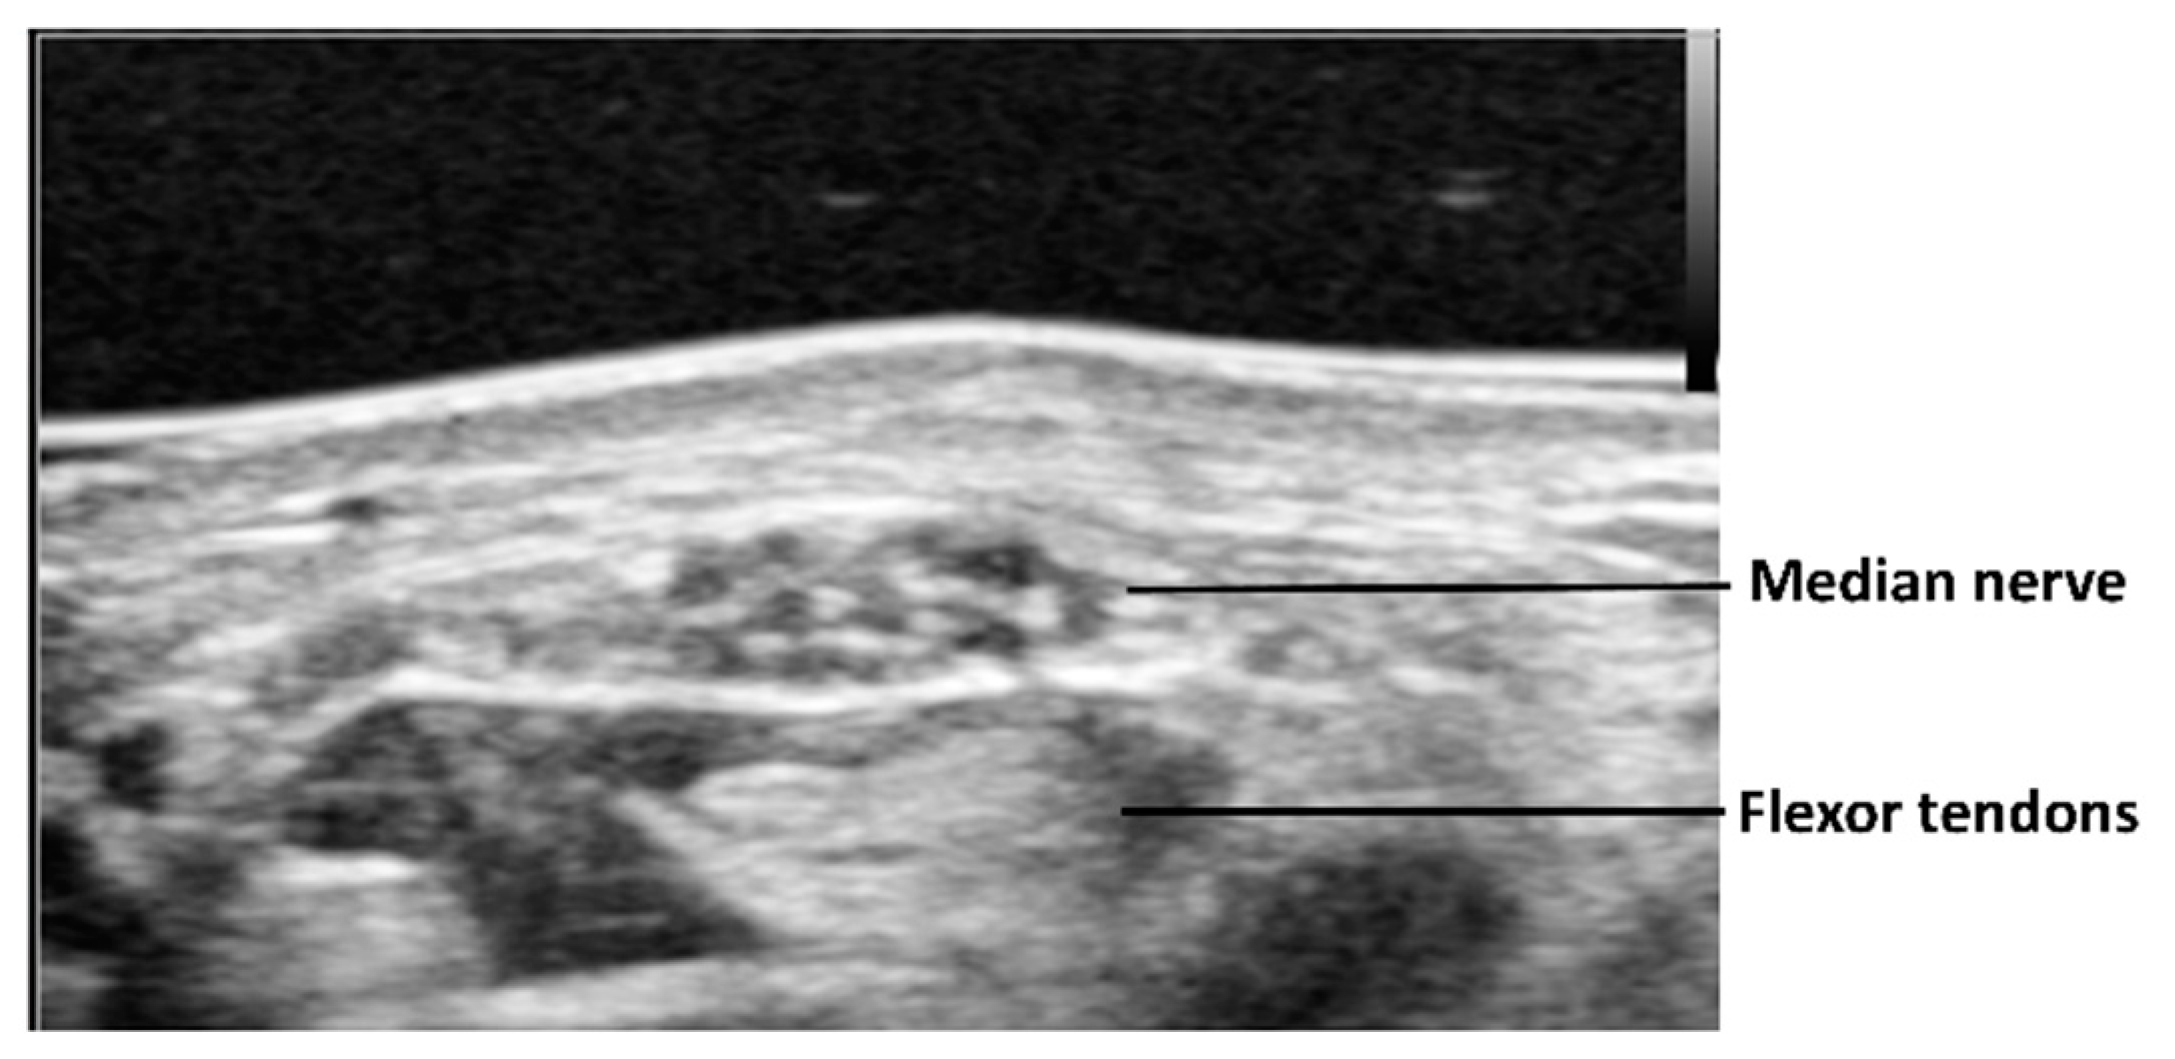

Figure 1. A typical ultrasound image of median nerve at proximal carpal tunnel.

In the 1990s, it was well established in the literature that static ultrasound imaging could detect pathologies such as thickening and echogenicity alteration of the flexor tendons [13] and flexor retinaculum [14], synovial proliferation, swelling of the median nerve in the proximal part of the carpal tunnel, and flattening of the median nerve in the carpal tunnel [15,16,17]. Also, restricted motion of the median nerve with different finger and wrist positions was demonstrated in patients with CTS [18,19]. Using cross-sectional ultrasound imaging, the median nerve is observed as a honeycomb structure surrounded by the hyperechoic epineurium (Figure 1). Morphological changes of the median nerve are expected in CTS, as the compression of the surrounding nonrigid structures alters its shape. This effect results in a reduction of nerve volume at the site of compression and increased size proximal (and sometimes distal) to the compression. Thus, the cross-sectional area of the median nerve is the most commonly applied criterion for diagnosing CTS on ultrasound. The cross-sectional area of the median nerve is obtained by visualizing the nerve perpendicular to its axis and tracing the nerve within its hyperechoic epineurium. It is easy to visualize the median nerve at the proximal carpal tunnel. However, at the middle or distal carpal tunnel, it is difficult to visualize. This is because the median nerve is deeper in the proximal palm than it is in the distal forearm or distal palm, and in the proximal palm it is covered by the thick flexor retinaculum. One report measured the cross-sectional area of the median nerve at three different levels: The distal edge of the flexor retinaculum, the hook of the hamate, and at the wrist crease [20]. The cross-sectional area was smaller in the central part than in the distal and proximal parts of the carpal tunnel, suggesting that the median nerve had an hourglass-like shape in cases of CTS. The median nerve is enlarged not only at the proximal to the carpal tunnel but also at the distal. Of course, this finding is frequently observed by surgeons clinically, during open carpal tunnel release surgery.